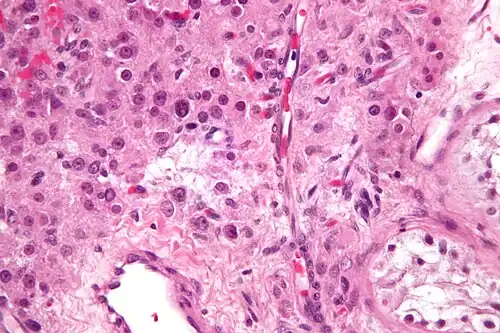

High magnification micrograph of a Leydig cell tumour. H&E stain.

High magnification micrograph of a Leydig cell tumour. H&E stain. -